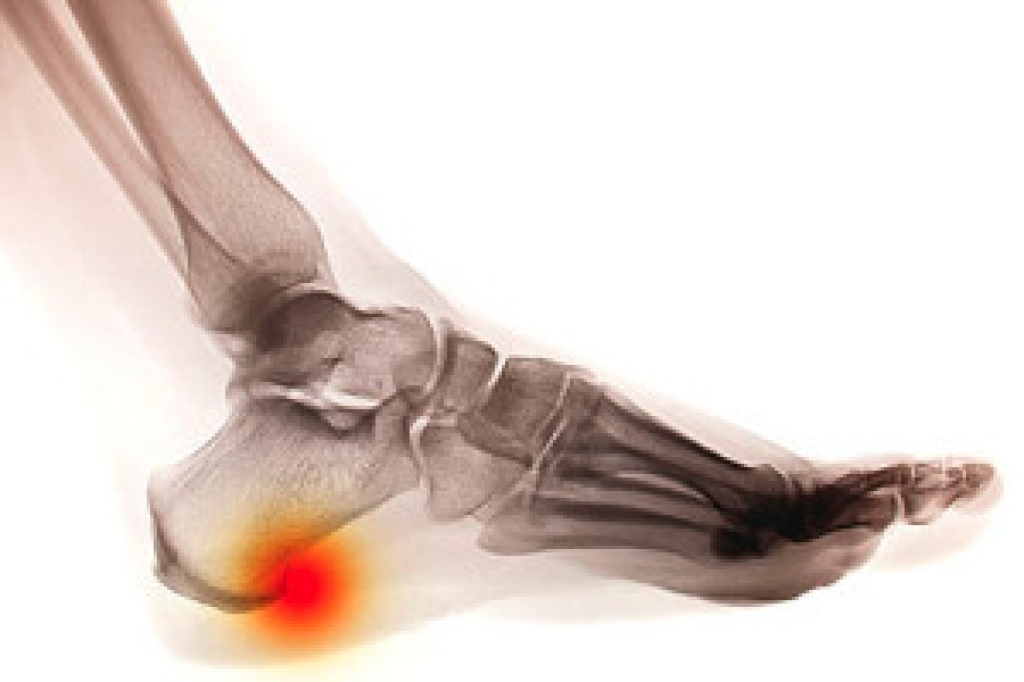

When the heel bone is under repeated stress, calcium deposits can form on the inside of it. These deposits, known as heel spurs, point towards the arch and can measure up to half an inch. Heel spurs can be associated with plantar fasciitis, and they are sometimes masked by the discomfort of that condition. Some heel spurs may not produce any symptoms, while others can be quite painful. You can try to get relief from a heel spur by using cold compresses or over-the-counter anti-inflammatories to reduce inflammation. Certain foot and calf stretches may also help to relieve pain as well. Patients who are struggling with heel pain that may be a heel spur should consult with a podiatrist.  A podiatrist can diagnose the source of the pain and offer more advanced forms of treatment.

Heel spurs can be incredibly painful and sometimes may make you unable to participate in physical activities. To get medical care for your heel spurs, contact Mack Jay Groves IV, DPM from Groves Foot & Ankle. Our doctor will do everything possible to treat your condition.

Heels Spurs

Heel spurs are formed by calcium deposits on the back of the foot where the heel is. This can also be caused by small fragments of bone breaking off one section of the foot, attaching onto the back of the foot. Heel spurs can also be bone growth on the back of the foot and may grow in the direction of the arch of the foot.

Older individuals usually suffer from heel spurs and pain sometimes intensifies with age. One of the main condition's spurs are related to is plantar fasciitis.